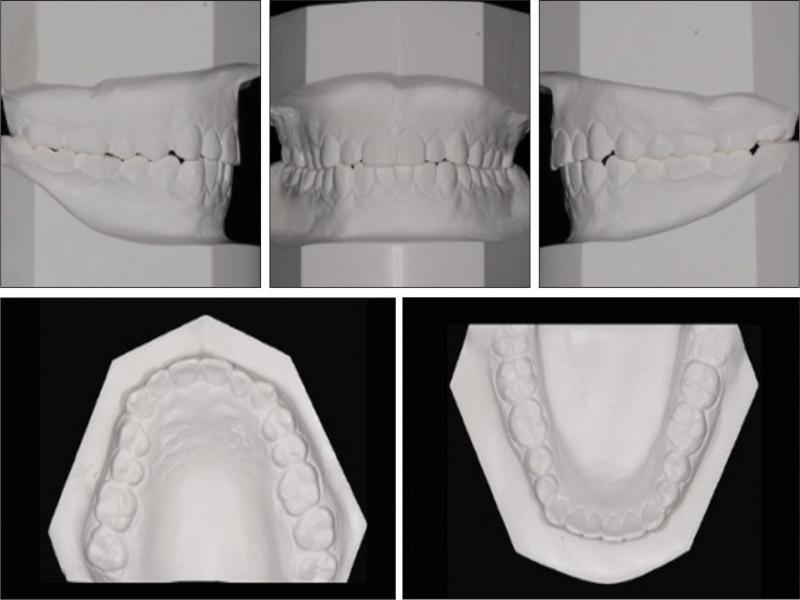

Pretreatment dental casts.